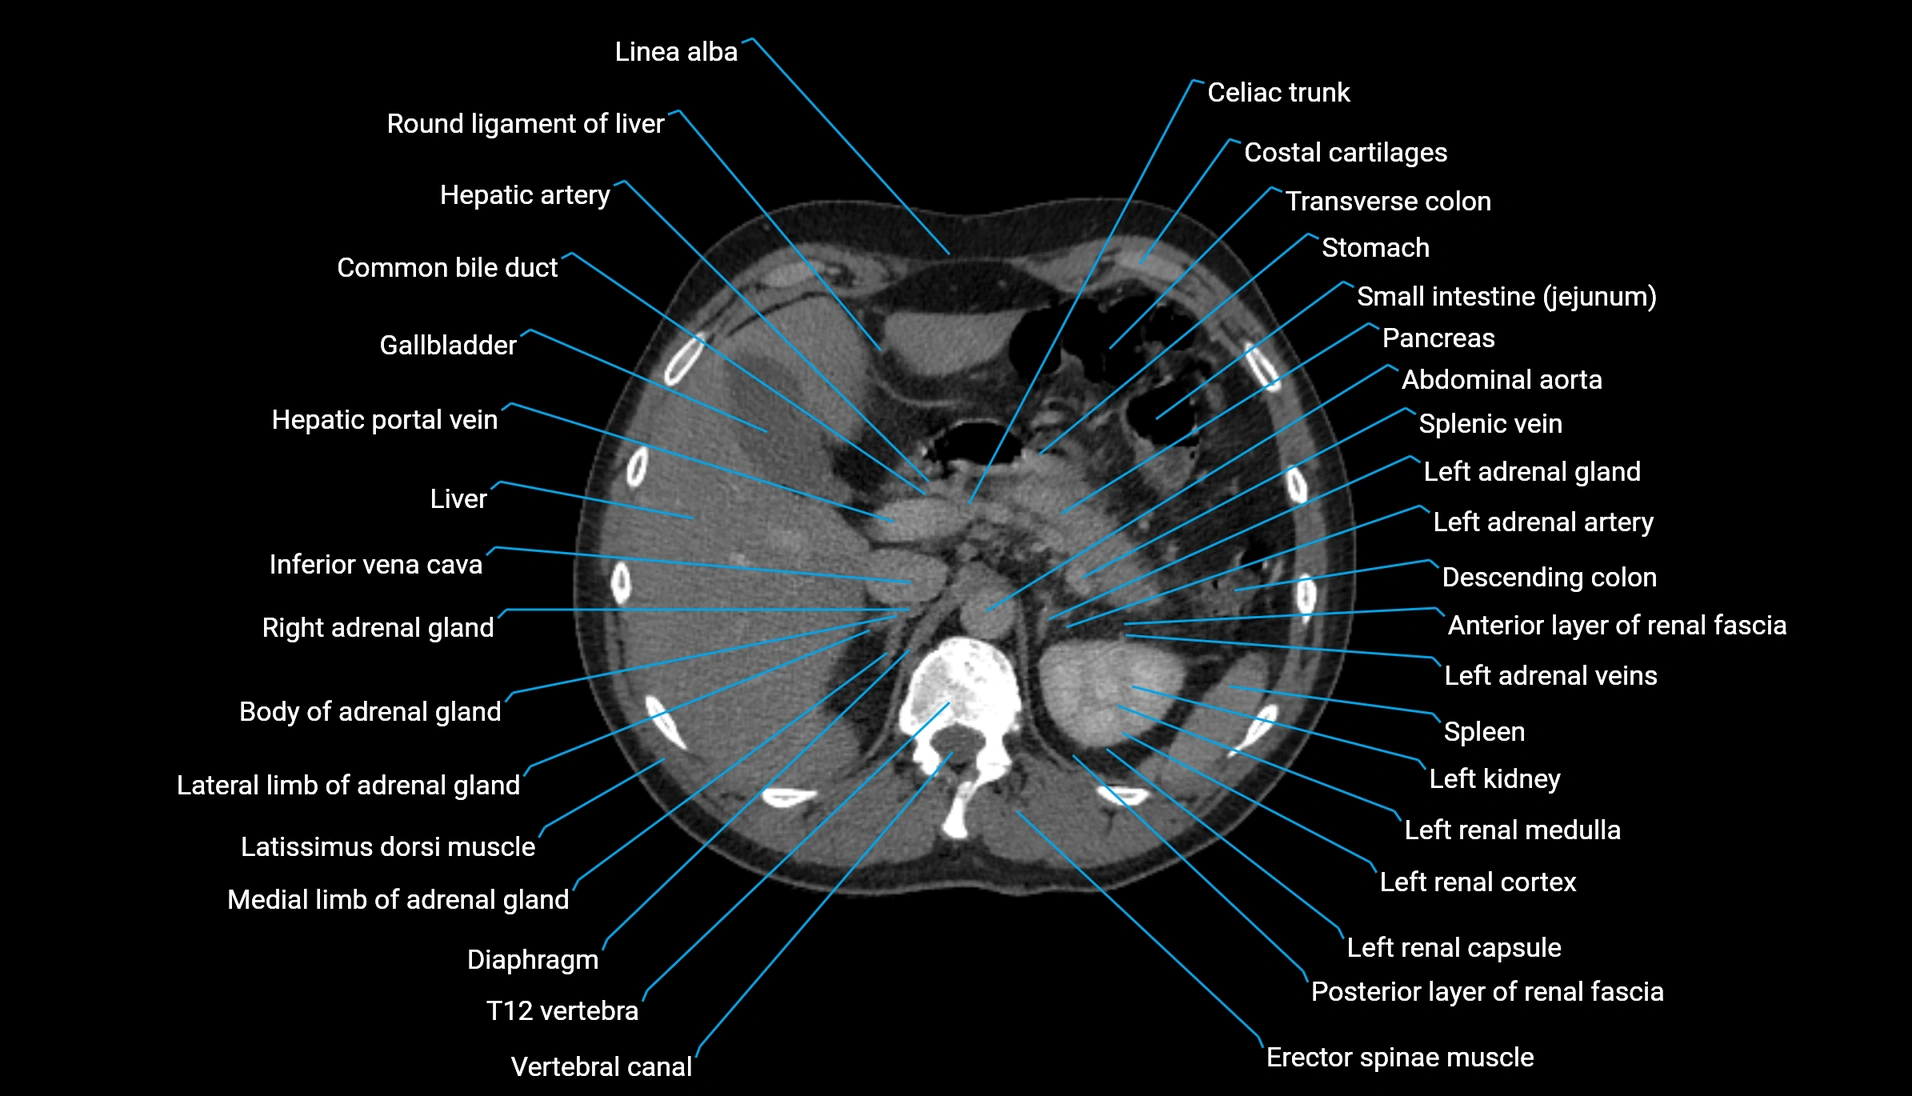

CT Appearance

Non-contrast CT:

-

Demonstrates cortical bone of acetabular rim in excellent detail

Detects fractures, dysplasia, retroversion, or bony overcoverage (pincer impingement)

3D reconstructions used in preoperative hip surgery planning

CT VRT 3D image

CT image